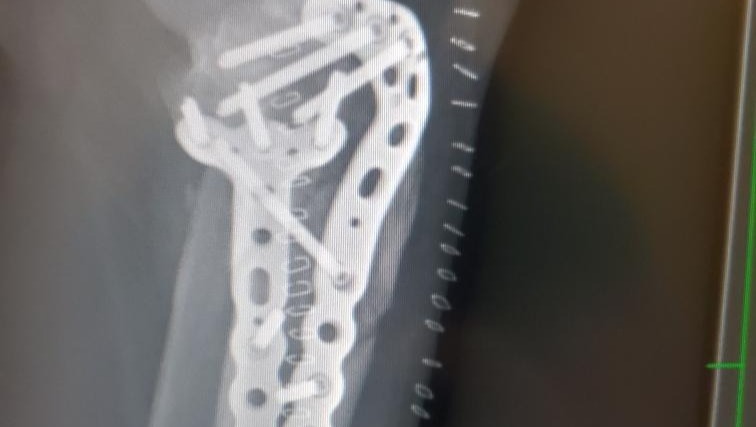

Surgery was needed to reset the bones and straighten my leg. I was put into an external fixation where they screwed this device into my bones to help me keep the bones in place while the swelling went down in my leg. This device was only supposed to be on for two weeks. At the follow-up to schedule the second surgery, the swelling had not gone down enough to put the plates and screws that would replace the external fixation. I was lucky that the fracture was not an open one and I was lucky to keep my leg because of how close the break was to my knee and how serious the fracture was to both bones.

I was in the external fixation for 3 weeks. Then I underwent the second surgery for the plates and screws. The surgery was supposed to be only 4 hours and it took almost 8 hours. According to the CT scan before the first surgery, the tibia bone had five fragments, however they found more during the surgery. I still could not put weight on my leg after the surgery. I was cleared for weight bearing at the beginning of November and had to learn how to walk again. I also had to retrain my brain to recognize my right leg again. I met my goal of walking with a cane before Christmas. I still have a limp and a long way to go before I am “100%” normal. The doctors think that I might not be 100%, but pretty close to it.